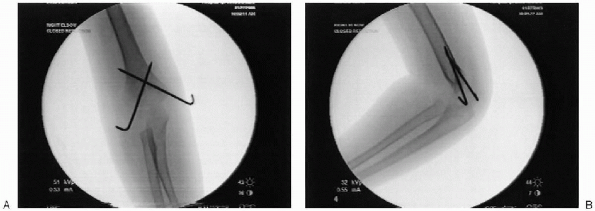

FIGURE 12-10. A: Demonstration of lateral column closed reduction. B: Pin fixation of lateral column.

FIGURE 12-11. Medial pin being inserted. Note anterior to posterior direction on lateral film.

four views (AP, lateral, internal oblique, and external oblique) to

confirm reduction. Motion at the fracture site should be evaluated

under image intensification (Fig. 12-12). Following acceptable reduction, the pins are cut and bent over to facilitate easy removal on follow-up.

FIGURE 12-12. A: Post reduction anteroposterior with pins crossing above the fracture. B: Post reduction lateral.